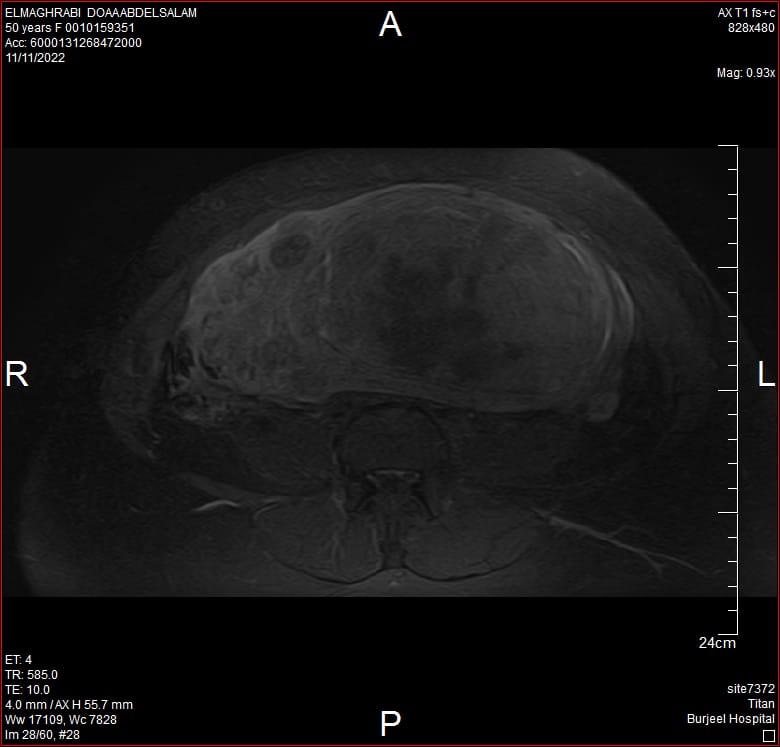

نجح أطباء مستشفى برجيل بأبوظبي في استئصال أورام رحمية من سيدة خمسينية مصرية الجنسية 52 عاما، بلغ وزنها 3 كيلوغرامات بطول 20 × 20 سنتيمتر بعد عملية جراحية معقدة أجرتها الدكتورة نضال العطية استشارية جرhحة النساء والتوليد والأورام والعقم.

وقالت الدكتورة العطية لـ "البيان" إن المريضة لم تكن تشعر بأية أعراض ناتجة عن هذه الأورام في أي مرحلة، وكانت تعتقد بأنها حامل، خاصة عندما أخبروها في إحدى المطارات بأنها حامل بسبب كبر البطن، وعند مراجعة المستشفى وإجراء التحاليل والأشعات اللازمة تبين عدم وجود حمل، ووجود مجموعة كبيرة من الأورام الحمية متداخلة مع أنسجة الرحم، مما استدعى تحديد موعد عاجل لإجراء الجراحة واستئصال الأورام.

وتابعت أن الإجراء الجراحي في حالات الأورام الليفية الحميدة يتم إجراء لاستئصال تلك الأورام بسهولة، ولكن في حالة هذه السيدة كان استئصال الأورام والرحم ضرورة حتمية خاصة أنها تجاوزت سن الإنجاب حيث أظهرت الإشاعات المختلفة أن الأورام متداخلة مع الرحم بنسبة كبيرة، مشيرة إلى أنه يراعى عند الاستعداد للجراحة عدة عوامل تأخذ بعين الاعتبار وهي التوقيت المناسب بحيث يتم الإجراء الجراحي بعد انقضاء الدورية الشهرية وربط الشريان الرحمي لعدم فقدان كمية كبيرة من الدم وإجراء فتحة صغيرة لاتتجاوز 5 سنتيمتر أسفل البطن تحت التخدير الكامل.